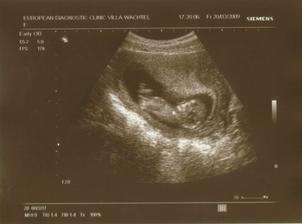

24.3.2009 NT biochem.screening - utz v pořádku, NT 1,9 mm, nosní kůstka přítomna, měříme 6,6cm, bylo to nááádherné přestavení 🙂 30.3.2009 celkové výsledky screeningu jsou v pořádku